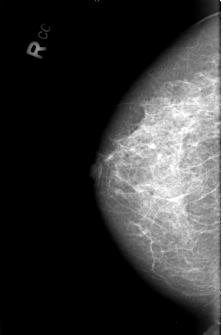

B_3007_1.RIGHT_CC

RIGHT_CC LINES 4344 PIXELS_PER_LINE 2888 BITS_PER_PIXEL 12 RESOLUTION 50 NON_OVERLAY